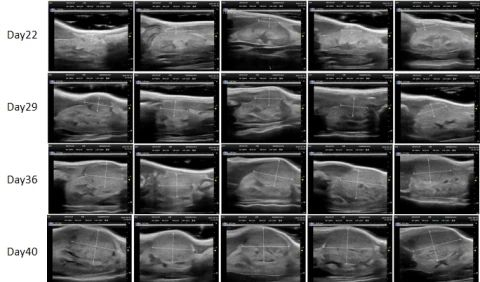

ʹÓó¬Éù¶àÆÕÀպͳ¬Éù»Ø²¨ÔÀí£¬£¬£¬£¬¿ÉÒÔÏÔʾ³ö¾Ö²¿ÓÐʵÖÊÐÔµÄÖ×Áö£¬£¬£¬£¬ÌØÊâÊÊÓÃÓÚÉöÔà¡¢ÒÈÏÙ¡¢Âѳ²¡¢°òë׵Ȳ¿Î»µÄÔλÖ×ÁöÄ£×Ó¼à²â¡£¡£¡£